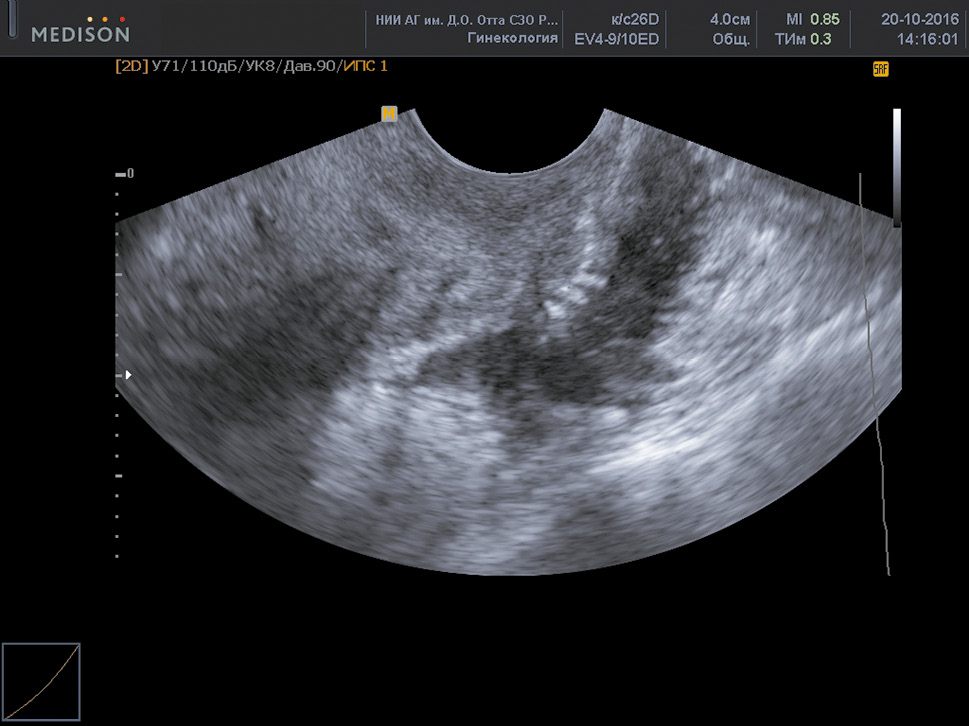

In most cases, cystic ovarian endometriosis had characteristic US signs, such as the location of the cyst behind and lateral to the uterus; medium and increased echogenicity of the “finely dispersed,” suspended material filling the cyst; and significant wall thickness (0.2–0.6 cm) (Fig. 1).

Fig. 1. Ovarian endometrioma

Рис. 1. Эндометриома яичника

Nonetheless, the suspended material in smaller cystic formations (up to 1.5 cm in diameter) is not always visualized clearly; therefore, the cyst may resemble a solid tumor. In addition, endometriomas are characterized by limitation of ovarian mobility during the US [10]. Ovarian endometriomas are often associated with other foci of endometriosis, such as deep infiltrating endometriosis (DIE) and peritoneal adhesions [11]. Notably, the symptom of “kissing ovaries” indicates severe adhesions in the lesser pelvis. Moreover, it was noted that endometriosis of the intestines and fallopian tubes is more common in women with the symptom of “kissing ovaries” than those without it (18.5% vs. 2.5% and 92.6% vs. 33%, respectively) [12]. Endometriomas can decidualize during pregnancy and can be mistaken for ovarian cancer on US imaging [13]. The simultaneous presence of other foci of endometriosis can accurately diagnose an endometrioid cyst during pregnancy and minimize unnecessary surgical interventions.